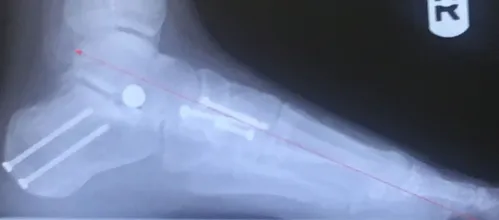

1. In MODERATE TO SEVERE cases a fourth procedure called a “posterior calcaneal osteotomy” is performed.  This procedure is performed through a small incision on the outside of the foot just behind the outer anklebone.  The heel bone is cut in an oblique fashion and slid to the inside of the foot.  It is held in position by two screws.  During the procedure the weightbearing portion of the heel bone is slid ¼” to almost ½” medially.  Weightbearing is reestablished in a more correct position as the heel bone is centered underneath the tibia and the Achilles tendon has a more natural tendency to turn the heel bone under (supinate) rather than turn out (pronate).  The heel bone is a well-vascularized bone that heals more quickly than the Achilles tendon, naviculocuneiform joint fusion or Cotton procedure.  The screws that are placed in the back of the heel under the skin are left in permanently.  We have found that when we are able to get the lower leg to be lined up perfectly straight with the heel bone we get a much better long-term outcome with a much less chance of recurrence of the deformity.

1. Some surgeons favor another procedure called an “Evans calcaneal osteotomy”.  It is a procedure that is performed on the outside of the back one-third of the foot.  In this procedure it is theorized that the outside of the foot is shorter than the inside of the foot and opening the heel bone and placing bone graft in the area will equalize the inner and outer columns of the foot.  When the procedure is carefully done, a bone graft from 6-10 mm is placed approximately 1 to 1.5 cm behind the calcaneal cuboid joint.  The outer portion of the foot is “swiveled or swung inward” and this helps to reestablish an arch in three planes.  Other procedures that are performed at the same time may include a lengthening of the Achilles tendon or gastroc.  For severe deformities a double calcaneal osteotomy, which includes an Evans and a posterior calcaneal osteotomy can be performed.  If during the procedure a “tripod” is not established, a naviculocuneiform fusion or a Cotton may be necessary to reestablish a normal plantar grade foot.  While we perform the Evans procedure, we typically prefer others so that complications which are more common in an “Evans” are avoided.  If necessary, an Evans procedure can always be performed at a later time.